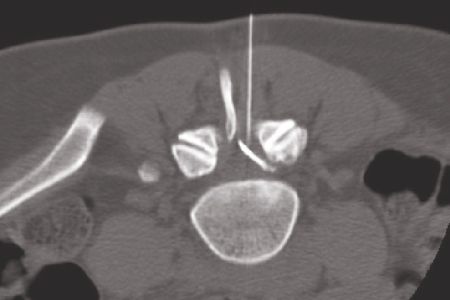

Die PRT ist eine Behandlung der betroffenen Nervenwurzel, die an der Hals-, Brust- und Lendenwirbelsäule durchgeführt werden kann. Unter MR- oder CT-Steuerung wird eine dünne Spezialsonde bis unmittelbar an die Nervenwurzel (entweder in der Nervenaustrittstelle (lateral) oder an den Spinalkanal (epidural) vorgeschoben. Zur Kontrolle wird ein Röntgenkontrastmittel durch die Nadel eingebracht, um die spätere Verteilung der Medikamente zu planen.

Durch die CT- Steuerung gelingt es, die Medikamente präzise an die Bandscheibe bzw. um die Nervenwurzel zu platzieren, die sich bis in den Wirbelkanal verteilen. So kann eine hohe örtliche Wirkdosis an der geschädigten Bandscheibe erreicht werden. Je nach Beschwerden wird in der Regel die Therapie vier- bis achtmal in Abständen von ca. zwei, später vier Wochen wiederholt.